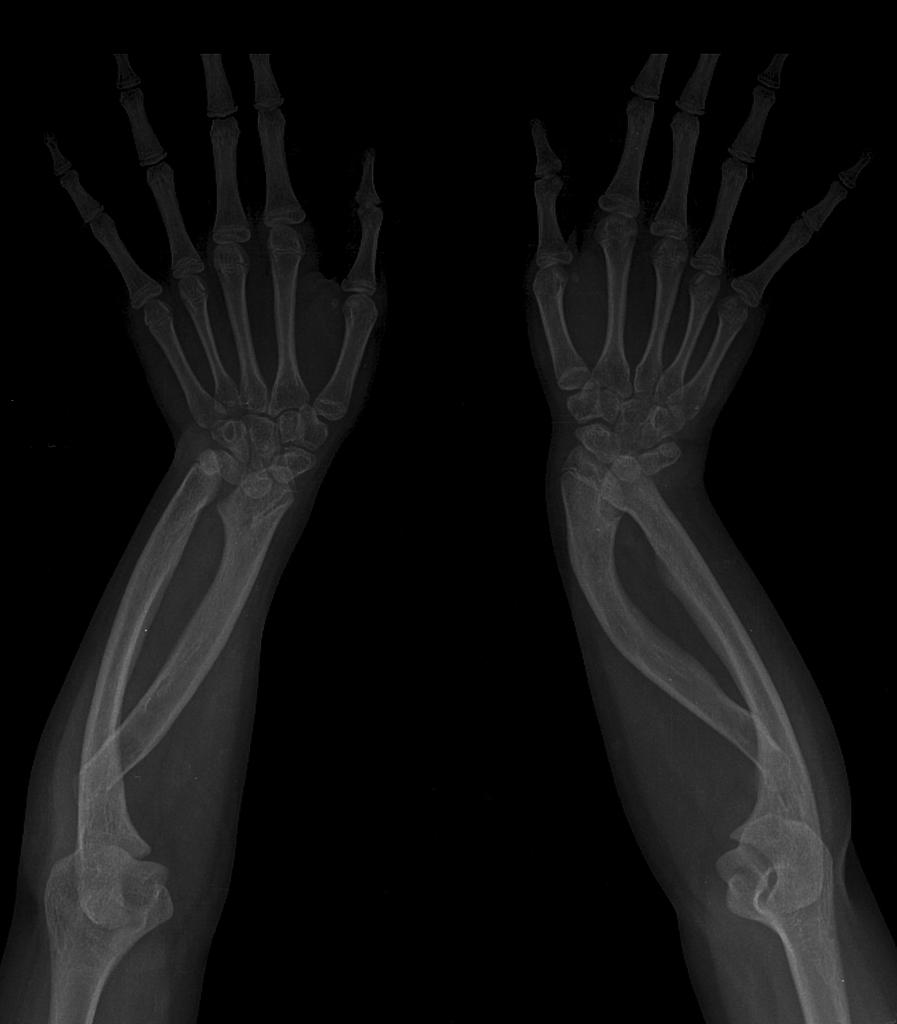

What is the Madelung deformity?

Madelung deformity is caused by epiphyseal growth plate disturbance at the ulnar side of distal radius, resulting in a short radius compared with the ulna.

Features of Madelung deformity

1. Shortening and bowing of radius bones causing dorsal subluxation of the distal radioulnar joint.

2. V-shaped proximal carpal row

3. positive ulnar variance.

4. pisiform can impacted against the ulna